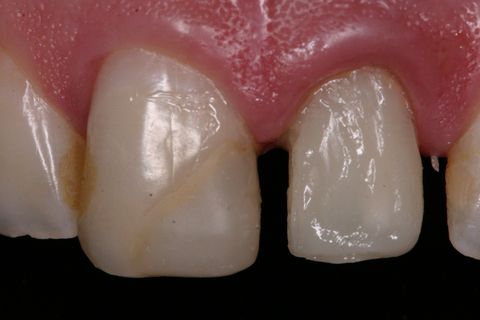

Aspecto Clínico Inicial

Aspecto clínico inicial (vista oclusal)

Paciente jovem do gênero masculino, apresentou-se à Clínica Integrada do Curso de Odontologia da Universidade Severino Sombra necessitando de um tratamento restaurador no dente 21. Ao exame clínico e radiográfico foi observado uma grande destruição coronária e tratamento endodontico satisfatório (Figuras 1, 2 e 3).